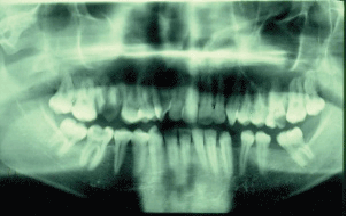

检查时,患者看起来很不舒服、易怒且不合作。右眼周围的肿胀很轻微,扩散到眶下区域。还发现右眼突出,内眦有脓液流出(图5).口腔内检查显示右侧颊部和上颌颊沟出现红斑和肿胀。右侧第一磨牙龋齿,易受撞击。正位x线片和根尖周x线片显示与第一磨牙相关的弥漫性根尖周透光性和右侧上颌窦混浊(图6)。

图6:在演示时轨道脓肿案例的Ortho-Pantomo-Graphic X射线视图,请注意右上右磨牙的感染剩余根